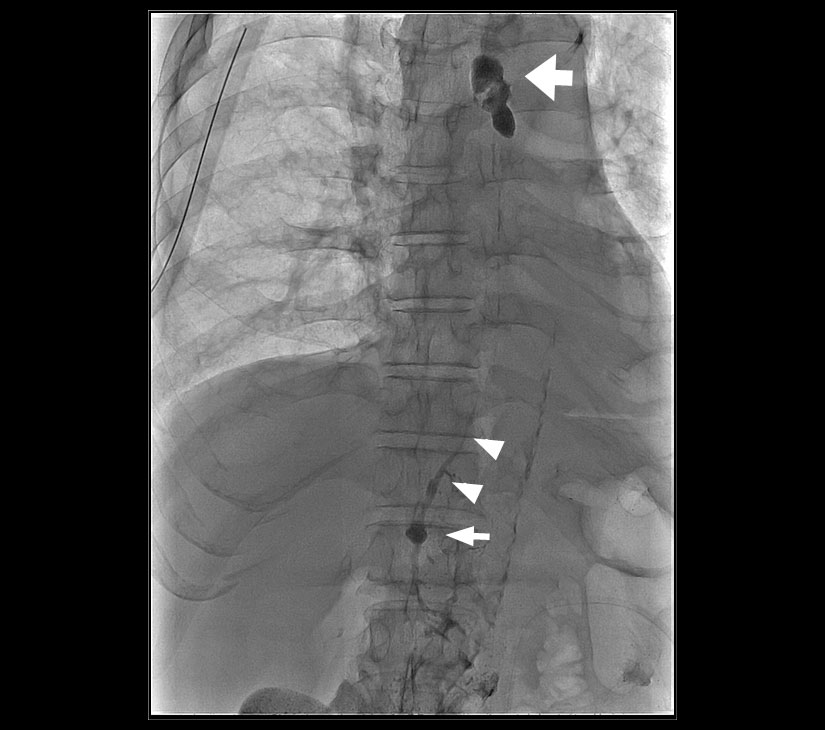

乳び胸、乳び腹水およびリンパ漏を含む、様々なリンパ液の漏出部を検出するために用いられるA Technical Review Korean J Radiol, 2014;15(6):724-732

- 本剤を皮膚直下の末梢リンパ管内に注入する。用量はヨード化ケシ油脂肪酸エチルエステルとして、通常、上腕片側 5~ 6 mL、下肢片側10mLである。注入速度は毎分0.3~0.5mL 程度が望ましい。